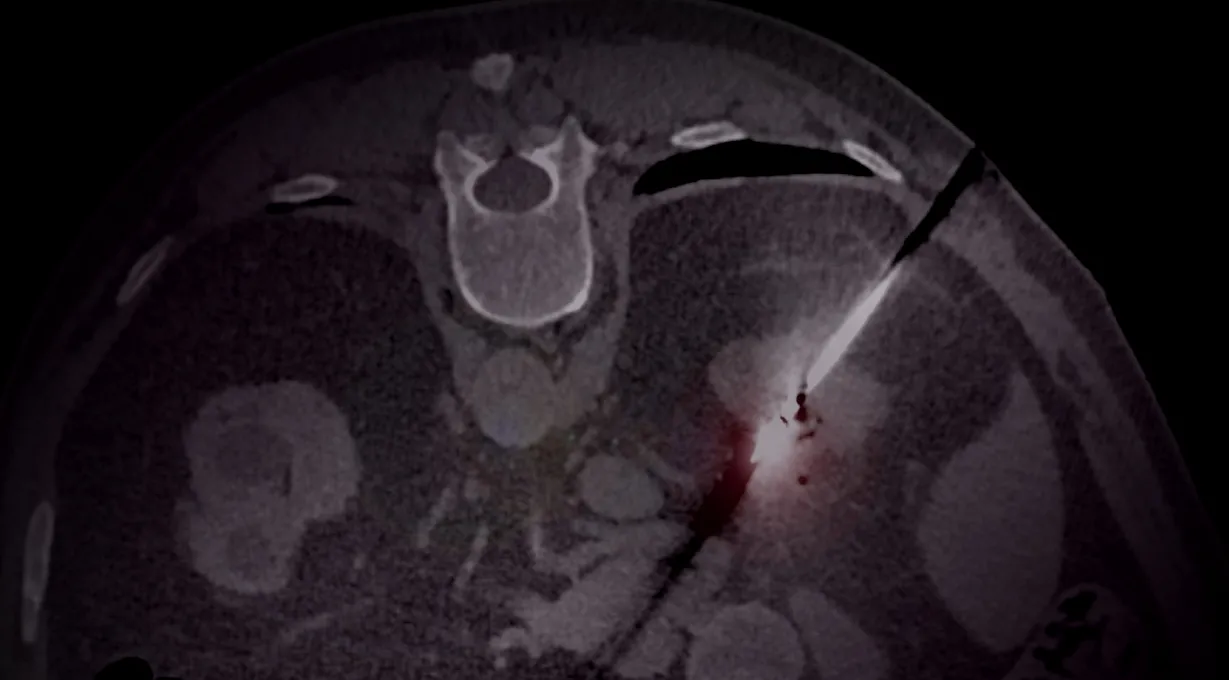

De perfecte manier om kennis te maken met een CT abdomen onderzoek! Leer de basics (o.a. verschillende soorten contrastonderzoeken) en maak kennis met een aantal veelvoorkomende ziektebeelden welke je tegen kan komen op een CT scan van het abdomen.

Ontdek de wereld van de interventieradiologie! Deze module biedt je een helder overzicht van de basisprincipes, de cruciale rollen van interventieradiologen en hun groeiende betekenis in de patientenzorg.

Benieuwd welke procedures een interventieradioloog uitvoert? Lees alles over de meest uitgevoerde niet-oncologische interventies, incl. indicaties en veelgebruikte technieken. Een mooie verdieping op module Interventieradiologie - Algemeen.